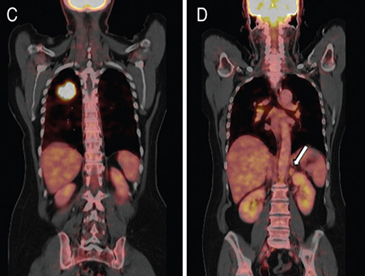

La gran mayoría de las lesiones malignas de la glándula suprarrenal presentan aumento en la captación del FDG (análogo de la glucosa) dado su mayor metabolismo glucídico; de modo contrario las masas benignas, no inflamatorias, no muestran captación significativa de este radiotrazador, como es el caso de los adenomas (Figura 15 a, b, c y d). Algunos estudios recientes reportan que el PET con FDG tiene una sensibilidad cercana al 100% y especificidad de aproximadamente un 80 a 100% en la diferenciación de lesiones benignas y malignas. La presencia de necrosis o hemorragia en una lesión maligna suprarrenal puede resultar en un falso negativo, así como también existe una baja sensibilidad en lesiones menores a 1 cm. En relación a los falsos positivos se ha reportado que un 5% de los adenomas y las lesiones de carácter inflamatorio-infeccioso pueden presentar leve captación del FDG.

El uso del PET incluido en un equipo de TC (PET-CT) ofrece claras ventajas con respecto al uso del PET en forma aislada, puesto que permite una mejor localización anatómica de las alteraciones metabólicas observadas, así como también puede incorporar la densitometría y las características de lavado ya descritas para la TC, lo que haría que tres de las técnicas más efectivas en la caracterización de las lesiones suprarrenales puedan combinarse en un solo estudio; bajo estas condiciones la sensibilidad y especificidad serían cercanas al 100%.

El PET-CT presenta utilidad en demostrar enfermedad oculta y enfermedad residual hipermetabólica cuando los hallazgos morfológicos son equívocos14. Esto cobra especial relevancia en casos en que la glándula suprarrenal es el único sitio de metástasis sospechado (Figura 21 a, b y c).